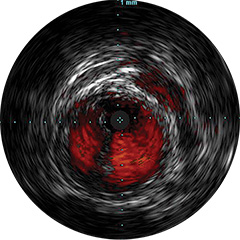

Figura 4

Digital IVUS imaging

Presentamos la nueva plataforma de aplicaciones intervencionistas Philips IntraSight, en la que la imagen, la fisiología, el corregistro* y el software se unen para facilitar una atención óptima del paciente. IntraSight ofrece un conjunto completo de modalidades clínicamente probadas, como la iFR/FFR, la IVUS y el corregistro* para simplificar las intervenciones complejas, acelerar los procedimientos rutinarios y proporcionar una mejor atención al paciente.